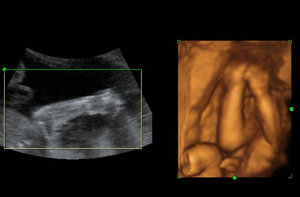

四维彩超——清晰目睹腹中宝宝的容颜

专家解释,如今的四维彩超与传统的B超检查有着很大的不同,我们通过四维彩超仪器能清晰地看出小宝宝的五官,同时还能观察到胎儿在母体腹中的运动过程,还能看到宫内胎儿打哈欠、伸懒腰等可爱的模样,让准妈妈与小宝宝第一次进行亲密接触。